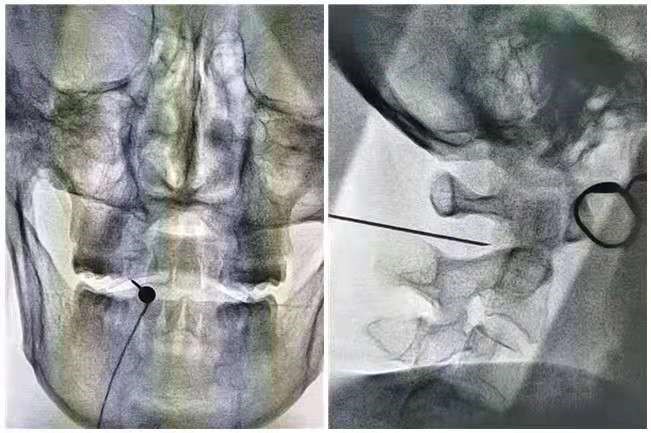

近日我院疼痛科乌日勒格副主任医师、翟志超主治医师在介入手术室医护的配合下成功为一顽固颈源性头痛患者行颈2脊神经节射频脉冲术,成功解决了长期困扰患者的头痛问题。

患者女,50岁,退休人员,头部疼痛10余年,以双侧枕部为主,严重时可放射至前额,为持续性钝痛偶伴过电样剧烈疼痛,严重影响日常生活及睡眠。曾多次行中医针灸及药物注射治疗,治疗期间疼痛有所缓解,停止后再次复发,如此反复,精神因长期遭受痛苦折磨而萎靡。患者及家属为减轻疼痛,提高生活质量,故来我院就诊。经过专科查体及相关检查结果判读,诊断为“颈源性头痛”,收治住院。针对反复发作的顽固性头痛,乌日勒格副主任医师决定为该患者行颈2脊神经节射频脉冲术。术后该患者立即感觉头痛、头部昏沉感消失,除了局部轻微麻木外,感觉非常轻松,睡眠也有明显改善,患者对此次治疗效果十分满意。

颈源性头痛是临床常见的疾病,指由颈椎、颈部软组织的器质性或功能性病损所引起的以慢性头部疼痛为主要表现的综合症。传统的治疗方法包括药物治疗、物理治疗以及枕神经阻滞等,但存在部分疗效不佳或有效性不长的缺点。脉冲射频对神经无破坏性影响,可能通过背根节外周突抑制周围神经C纤维伤害性传入和刺激背根节中枢突激活脑干下行抑制系统产生镇痛作用。采用放射线引导下颈2脊神经节脉冲射频术,整个治疗过程,安全、微创、有效。